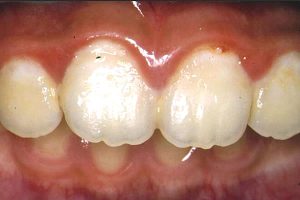

どうも我々は、“悪いところ探しをするクセ”を持っているようだ。

いつの間にそんなクセが付いてしまったのだろう?

きっと雑誌などで、理想的な口腔の写真ばかりを見ているからに違いない。

理想像と比較をすれば、目の前の口腔が悪く見えてしまう。

そう!

比較すべきものは、理想ではないのだ。